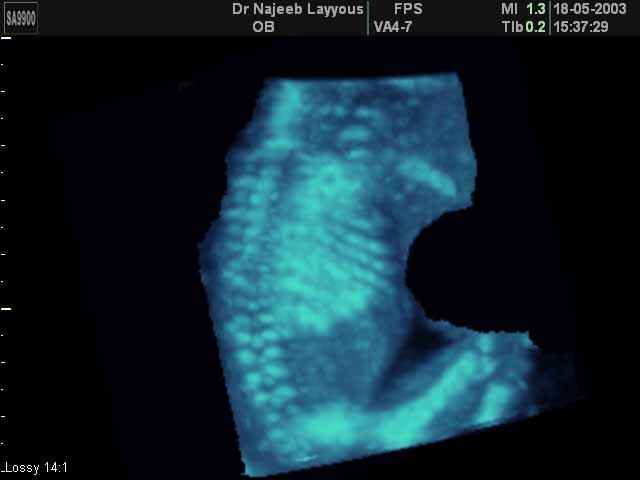

- 3D Photos échographie du squelette du fœtus